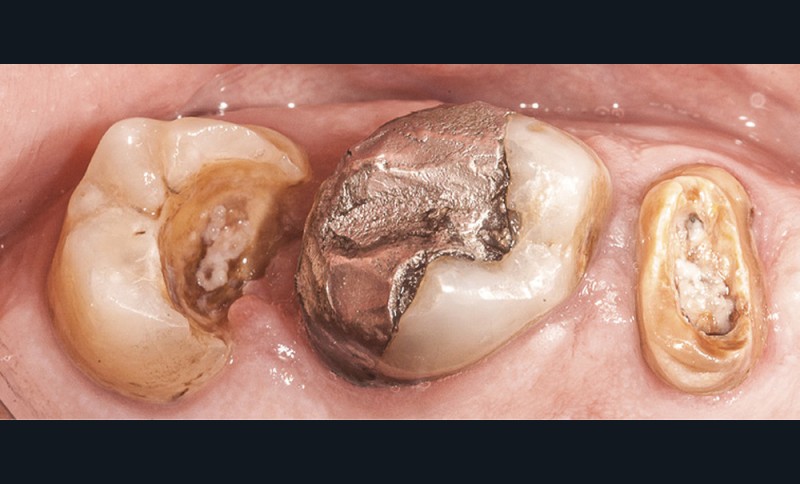

En dentisterie restauratrice, la tendance actuelle est, dans la mesure du possible, de « copier la dent naturelle grâce aux restaurations adhésives en céramique » [1]. Cependant, les tissus dentaires sont soumis à différents « outrages » qui peuvent être à l’origine de pertes de substance parfois très importantes. Contrairement à ce que l’on peut penser, et ce malgré les progrès indéniables rendus possibles par la prévention dans cette spécialité, le praticien se trouve encore trop souvent confronté à des pertes de substance majeures, voire irrémédiables (fig. 1). L’évaluation précise de la qualité des tissus résiduels constitue une étape essentielle permettant au praticien de proposer une thérapeutique adaptée au patient [2].